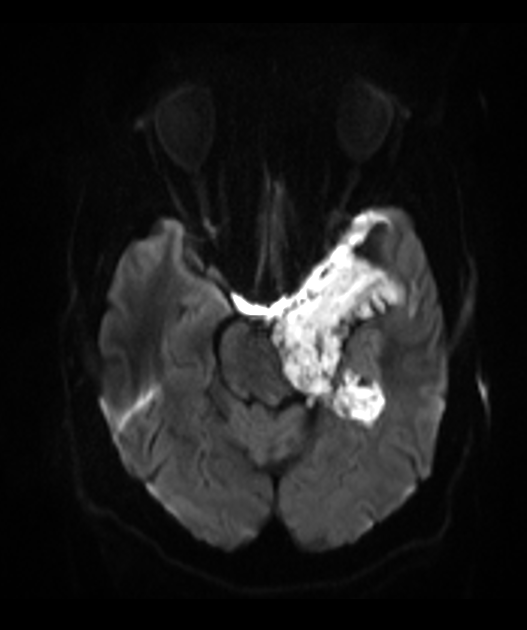

- DWI: Marked restriction (key diagnostic feature)

- "Popcorn" appearance on DWI due to lamellated keratin

- 60-year-old patient present with ataxia and poor left-sided hearing.

- MRI showed a T2-hyperintense non-enhancing lobulated lesion with low ADC values in the left side of the posterior fossa, encasing the 7th and 8th nerve complexes.

- There was significant mass effect on the cerebellum (presumably relevant to the ataxia) but there was no oedema, indicating that this lesion has grown slowly.